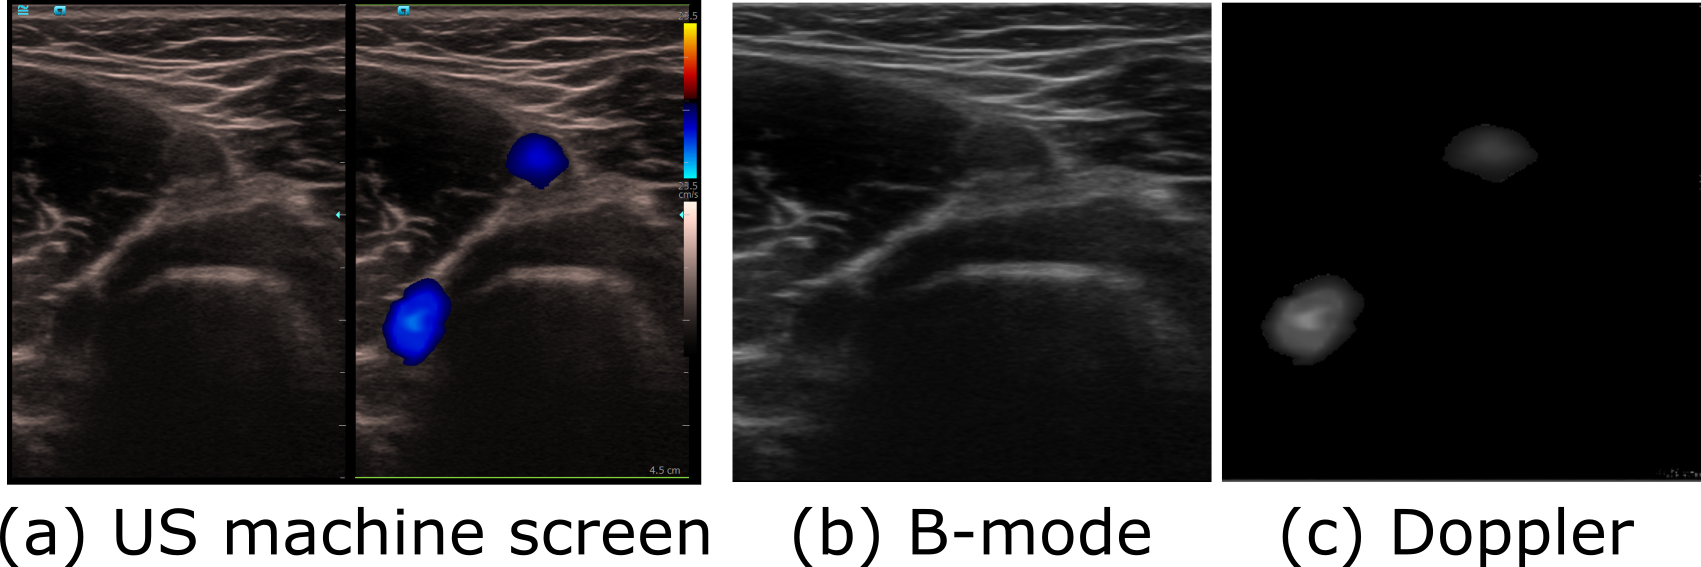

Refer to caption

Figure 2: Illustration of the pre-processing pipeline.

III-A2 Duplex Data Pre-Processing

The frame grabber can only provide access to the same images displayed on the US machine screen Fig. 2 (a). In order to segment the US images and further visualize the segmented binary masks in 3D in real-time, online pre-processing was necessary. The received images [Fig. 2 (a)] were processed to generate B-mode images [Fig. 2 (b)] and Doppler images [Fig. 2 (c)], respectively. To extract Doppler features, the recorded images were converted to the HSV color space. Thereby, the colored Doppler features (blue or red in Fig. 2 (a)) can be easily extracted by setting a threshold in terms of saturation (100absent100\geq 100) and value (20absent20\geq 20). To reduce the number of input parameters, both duplex images were compressed to 320×320320320320\times 320 pixels for the segmentation network. The original size of the images was 497×733497733497\times 733 pixels. It should be noted that this downsampling procedure may introduce some degree of distortion and possible information loss. However, we deem it acceptable given that the blood vessels in question occupy a contiguous area that remains discernible in the lower-resolution representation. The implementation of the pre-processing pipeline was done using the open-source library OpenCV [32].